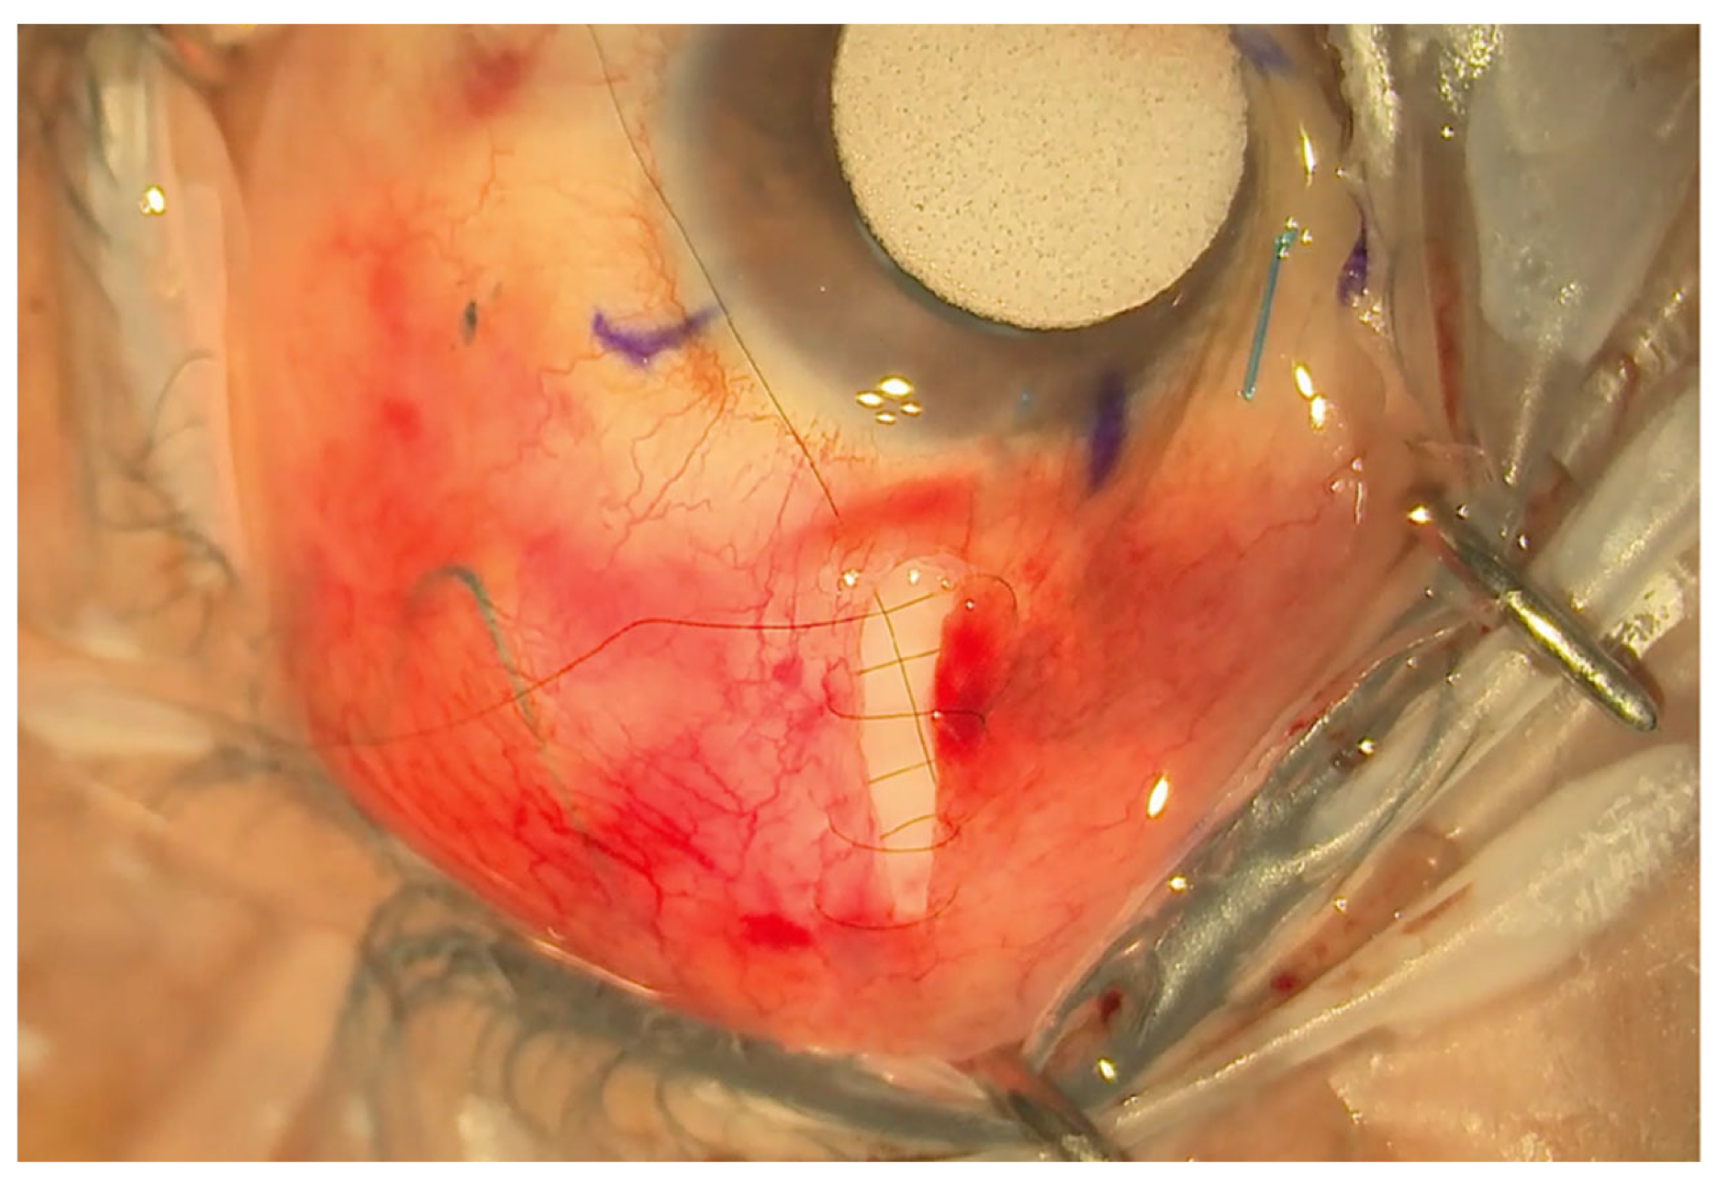

Figure 2.

Limbal sparing radial pocket. This is placed 5 mm behind the limbus and extended approximately 8–10 mm posteriorly.

The eyePlate-300 is ideally placed in the superotemporal quadrant. A 7/0 silk corneal traction suture is placed, and the eye is retracted inferonasally to expose the superotemporal quadrant. To create the conjunctival pocket, a subconjunctival injection of bupivacaine with adrenaline is injected behind the limbus mid-way between the superior and lateral rectus. This step helps to ensure adequate exposure of the conjunctiva and induces haemostasis. A vertical radial incision is then made 5 mm behind the corneal limbus with spring scissors extending posteriorly, approximately 8–10 mm in length. The conjunctiva is then dissected through this pocket to expose the bare sclera up to the lateral and superior recti. Haemostasis is further augmented with the use of cautery as required.

A 4/0 prolene suture is then fed into the tube to stent the eyePlate-300 tube. The eyePlate-300 can then be manipulated with Moorfields and Jayles forceps to be folded “Taco Style’ (Figure 1b) before being inserted on the sclera through the small conjunctival pocket (Figure 2). Care should be taken to unfold the plate under the tenons. Identification of the lateral and superior rectus muscles should take place to ensure the plate sits between the muscles, therefore minimising the risk of post-operative diplopia.